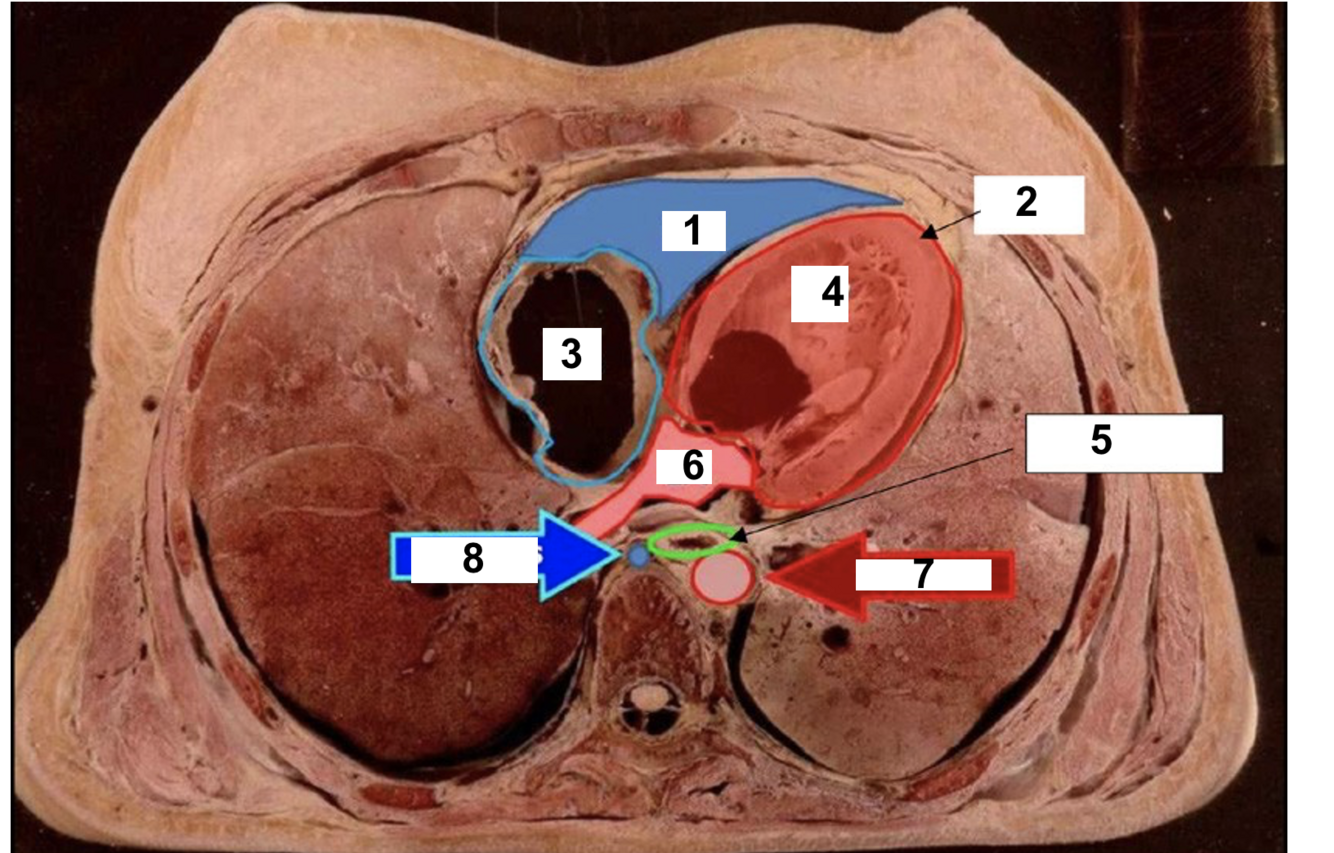

label 1

RV

2

Apex

3

RA

Q

A

18

5

oesophagus

19

6

LA

20

7

aorta

21

8

azygos vein